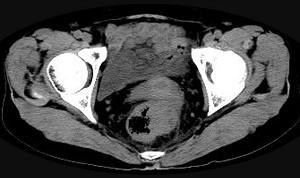

问题 男,56岁,排便形状改变,便不尽感,CT检查如图所示,下列说法正确的是 ( )

选项 A、此为直肠息肉 B、此为直肠癌 C、其表面光滑,边界清楚 D、肠腔未见狭窄 E、肠壁上有蒂状新生物 单选题

答案 B